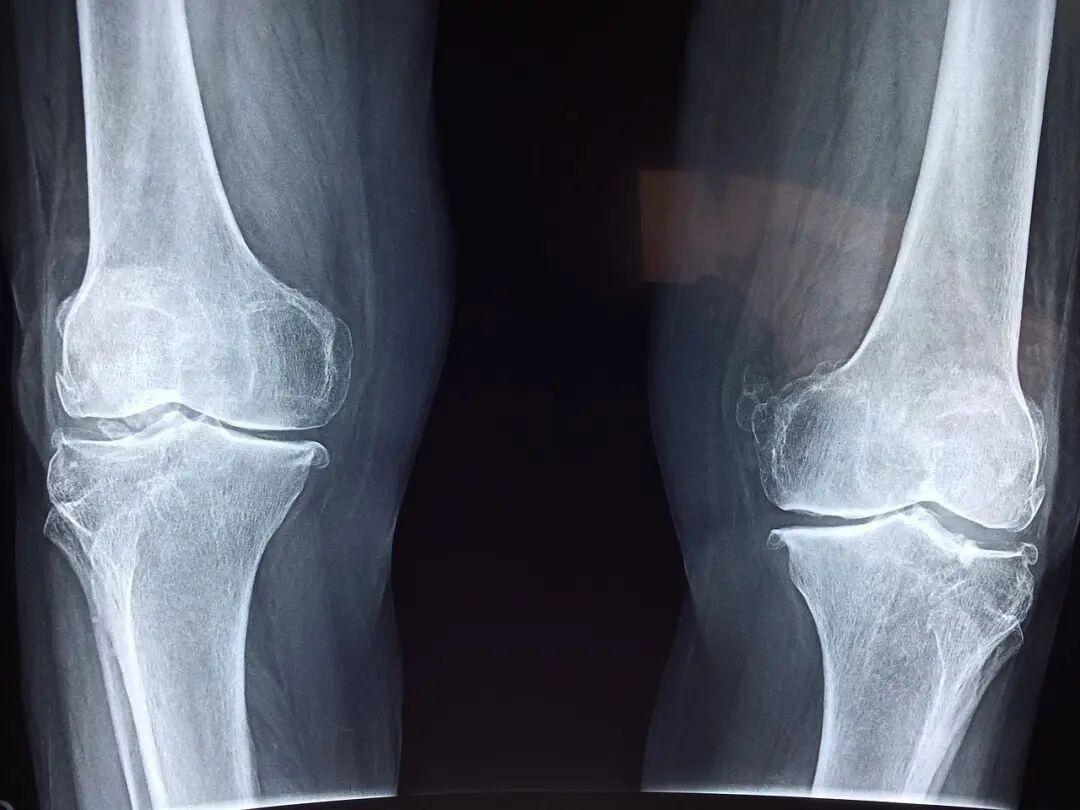

3:骨质疏松

骨质疏松是一种常见的退化性骨折风险因素,可能会导致严重的关节疼痛和功能障碍。在这里,我们介绍一下骨质疏松会如何影响你的下半身,特别是你的膝盖。

骨质疏松最常影响你的大多数大骨头,比如说你的四肢中最大的骨头(即手和脚)。

4:关节滑膜炎

突然发软的膝盖,很可能是因为关节滑膜炎。关节滑膜炎是一种常见的关节疾病,主要影响关节滑膜。这种疾病会导致关节不能正常运动,并且会出现疼痛和肿胀。

在大多数情况下,关节滑膜炎是由于过度使用或者受到创伤所引起的。长时间使用关节,或者受到创伤,都有可能导致关节滑膜的损伤。当关节滑膜受到损伤时,就会出现关节滑膜炎。